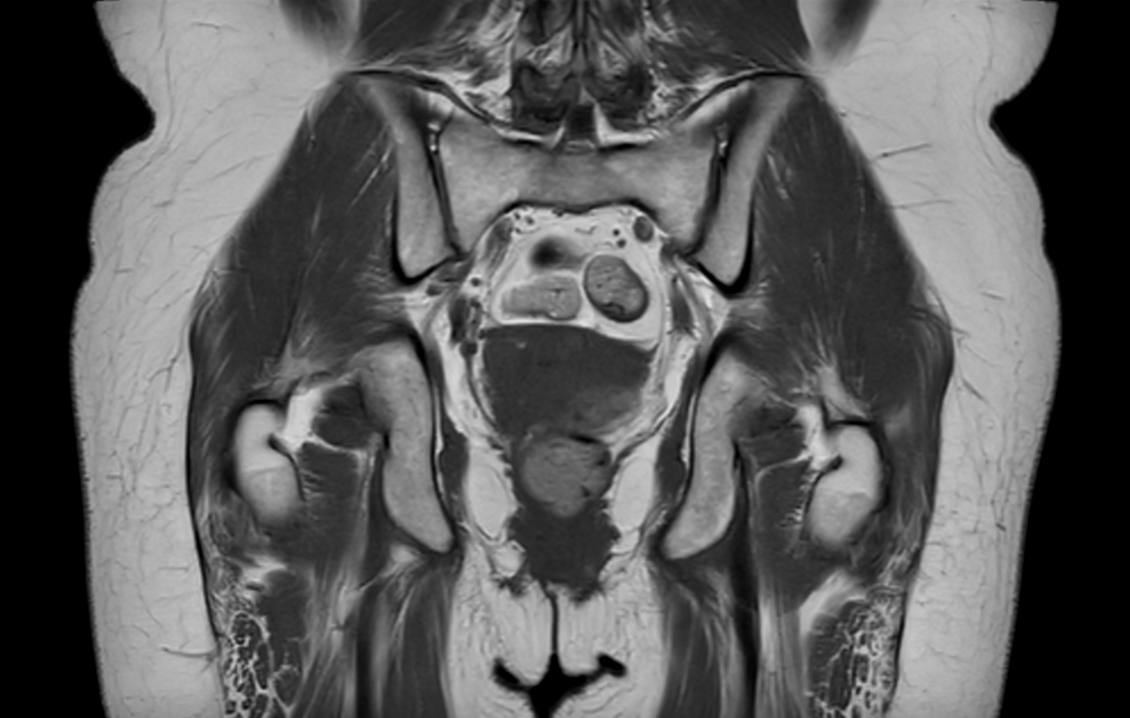

Coronal T1w TSE